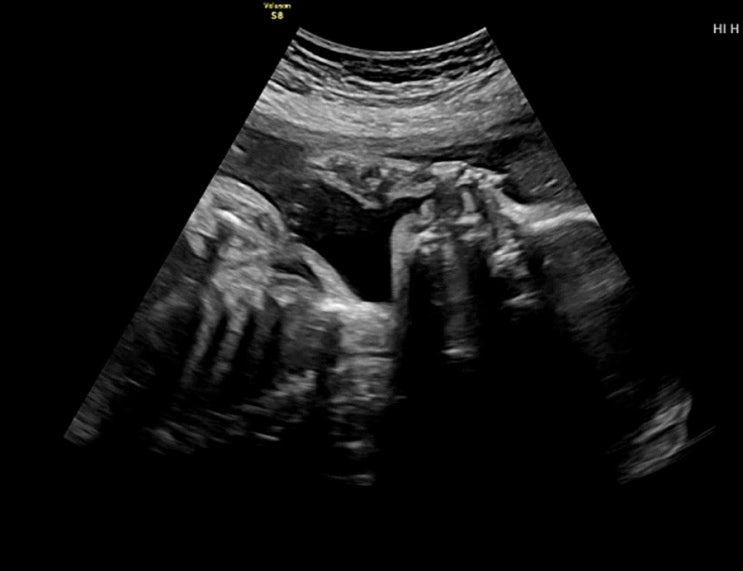

[28주 임산부] 주수대비 작은 태아, 신장(콩팥) 비대칭, 장 하얗게 보임 등 대학병원 후기

정말 얼마나 울었을까요,, 기억도 안나요 그냥 갑자기 눈물이 나고 정말 쉬지 않고 울었던거 같아요 갑자기...